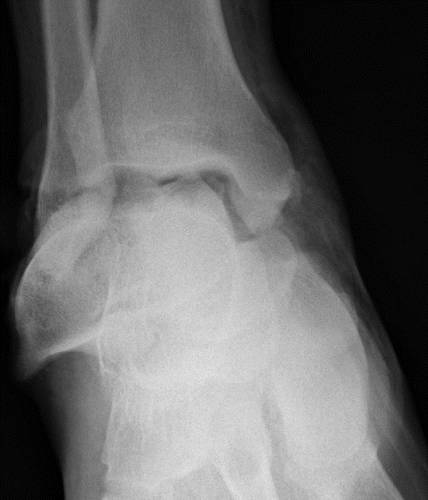

这种损伤必须与三角骨 - 一个附件后骨小梁区分开来。 在放射照相术中,后过程的断裂显示不规则的边缘(图13),而三角骨是圆形或椭圆形,具有光滑的皮质边缘(图14)。 双侧X线照片的价值有限,因为据报道三分之二的病例是双侧的(32)。 如果射线照片不确定,应进行CT。

图14 三角骨。 踝部的侧面X线片显示在距骨后方的椭圆形皮质骨化(箭头)。